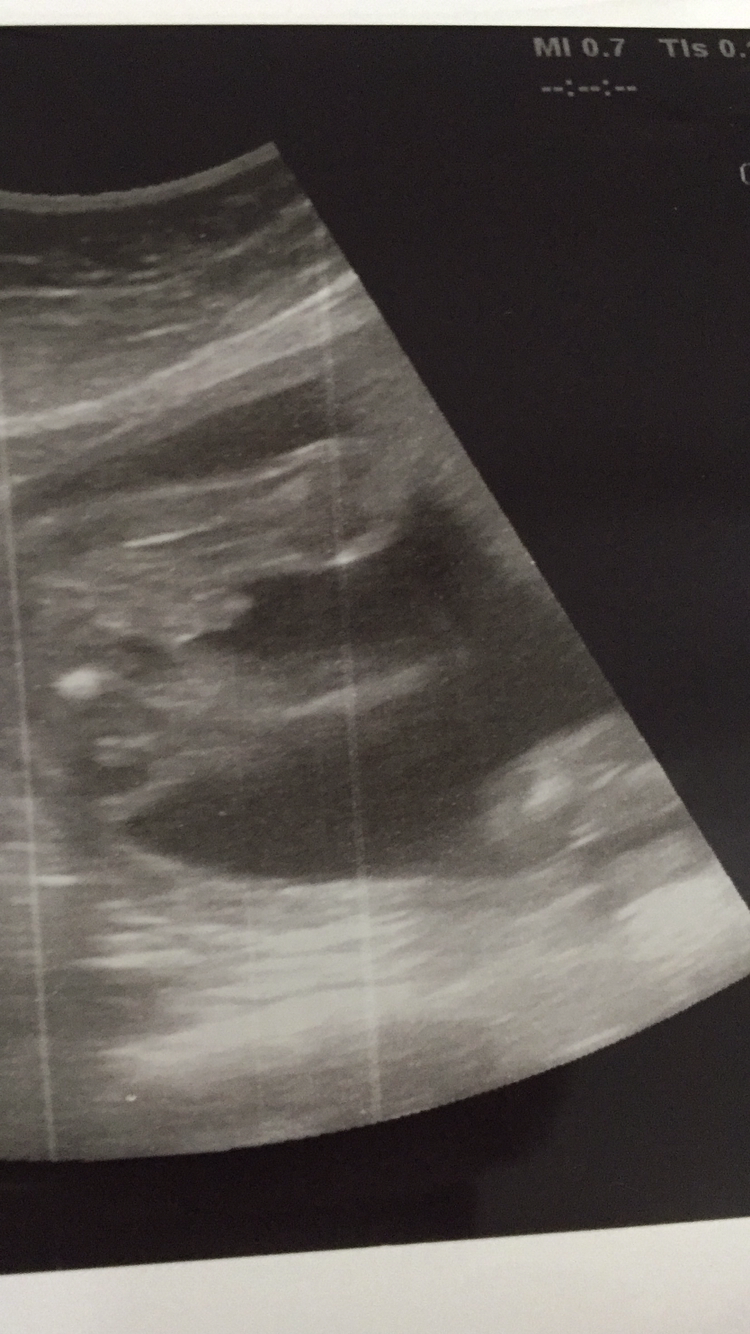

بنات هذا العضو صوره اليوم اظن في 22اسبواع تقول نص الخامس ولدتي تقول 11-4هجري

انت اليوم سويت سونار والا من قبل مسويته واليوم كان موعدك مع الدكتورة؟

لا هذا اليوم أشعه عاديه مع الدكتوره وقبل كان بس تفصيلي بدون الدكتوره